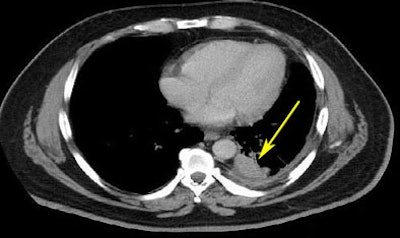

![]() |

| From the RIDER database, a lung cancer case is shown pretreatment (top) and post-treatment (bottom). |